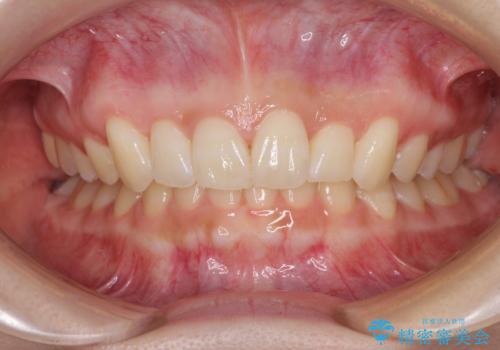

前歯のデコボコを治したい インビザライン矯正治療

- 前歯のデコボコ気になるとのことで来院された患者様です。

上下顎ともに歯列全体の後方移動とIPR(歯と歯の間を削る)によってデコボコが解消するように設計し、インビザラインにより治療を行うこととしました。

上下正中位置は、治療開始時よりは改善したものの、ここが限界であろうというところでのゴールとなりました。

下顎前歯の大半が隠れている状態ですが、左右への歯ぎしりはスムーズに行うことができ、就寝時には後戻り防止も兼ねて、食いしばり対策としてマウスピースの使用を継続するようお願いしております。